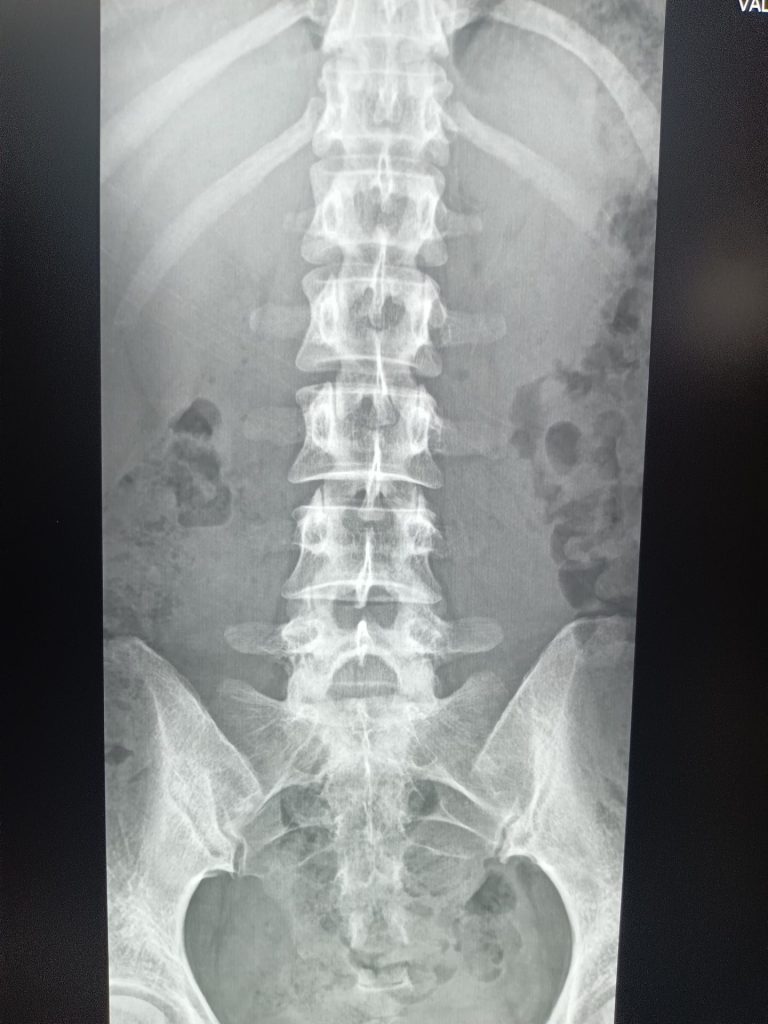

線量不足が原因で不鮮明な画像となっているX線写真(2枚目)と、適切な方法で撮影したX線写真(2枚目)

医師は左の画像で診断していたたため、右のように鮮明に撮影できるよう具体的な方法をレクチャーし、徐々に改善に向かっています。